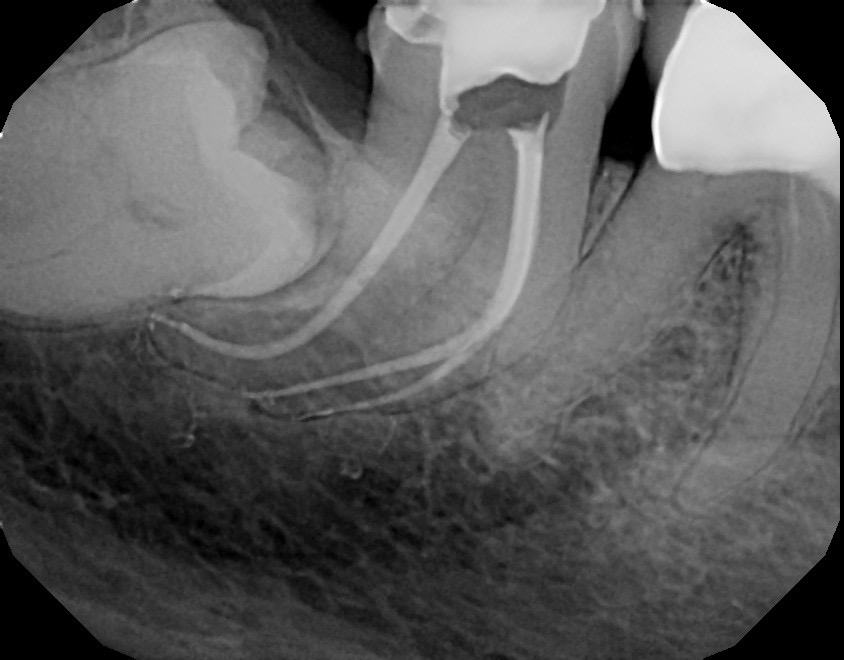

Tooth #31 cleaned and shaped with Edge File X7 .04 taper.